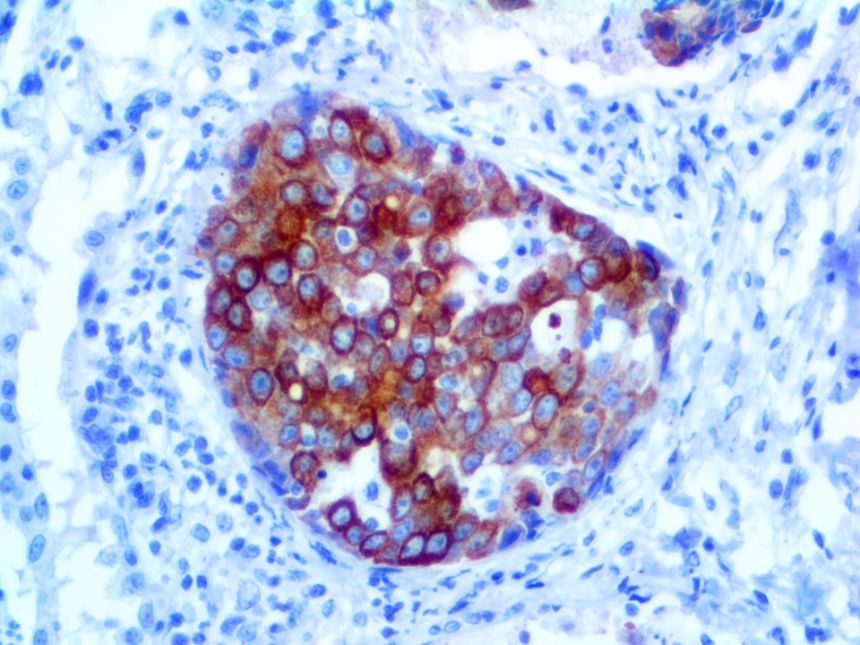

It is the ICU physician who is most likely to witness one of the deadliest manifestations of the abnormal immunological response, the cytokine storm syndrome (CSS). This response is also referred to by some as the cytokine release syndrome (CRS). CSS is characterized by continuous activation and expansion of macrophage and lymphocyte populations, which secrete large amounts of cytokines, causing the cytokine storm. This massive cytokine release is akin to hemophagocytic lymphohistiocytosis (HLH) disease, a syndrome characterized by initial unchecked and persistent activation of cytotoxic T lymphocytes and NK cells.

Clinical and laboratory manifestations of HLH include fever, enlarged liver and/or spleen, neurologic dysfunction, coagulopathy, liver dysfunction, cytopenias (i.e., low levels of erythrocytes, leukocytes, and/or platelets), hypertriglyceridemia, hyperferritinemia, hemophagocytosis, and eventually diminished NK cell activity as the immune system becomes progressively paralyzed. HLH can be familial (primary HLH) or secondary to another disease process (sHLH), such as rheumatic disease, in which it is referred to as macrophage activation syndrome (MAS, characterized by elevated ferritin).